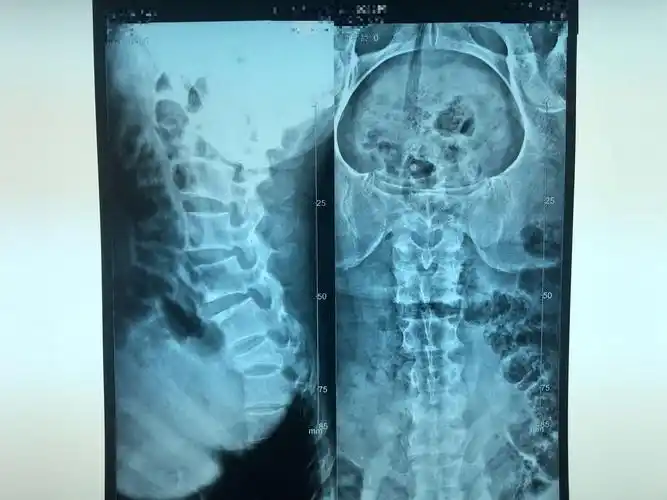

病例分享:胸12椎体压缩性骨折

胸椎(t12)压缩性骨折治疗记录 - 知乎